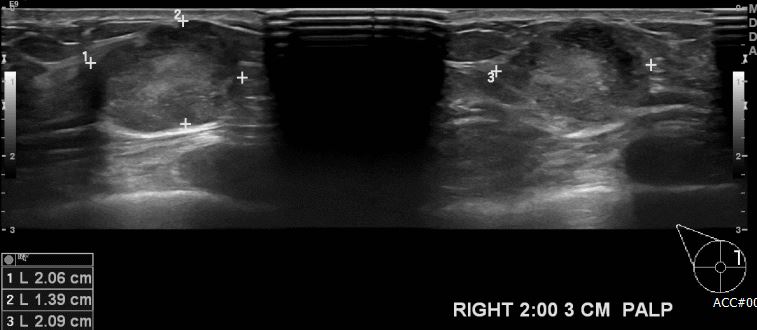

상기환자 우측 만져지는 멍울로 내원하신 40대 여성 분으로 우측 2시 방향에서 3cm 떨어진 거리의 만져지는 멍울 조직검사 시행하여 우측 점액성 침윤암 진단

되었습니다.